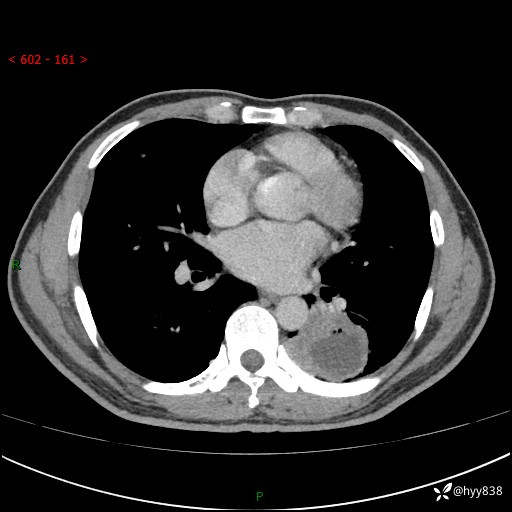

胸部CT平扫

增强

下肺占位,穿刺明确病理

影像是否典型,可否直击病理?